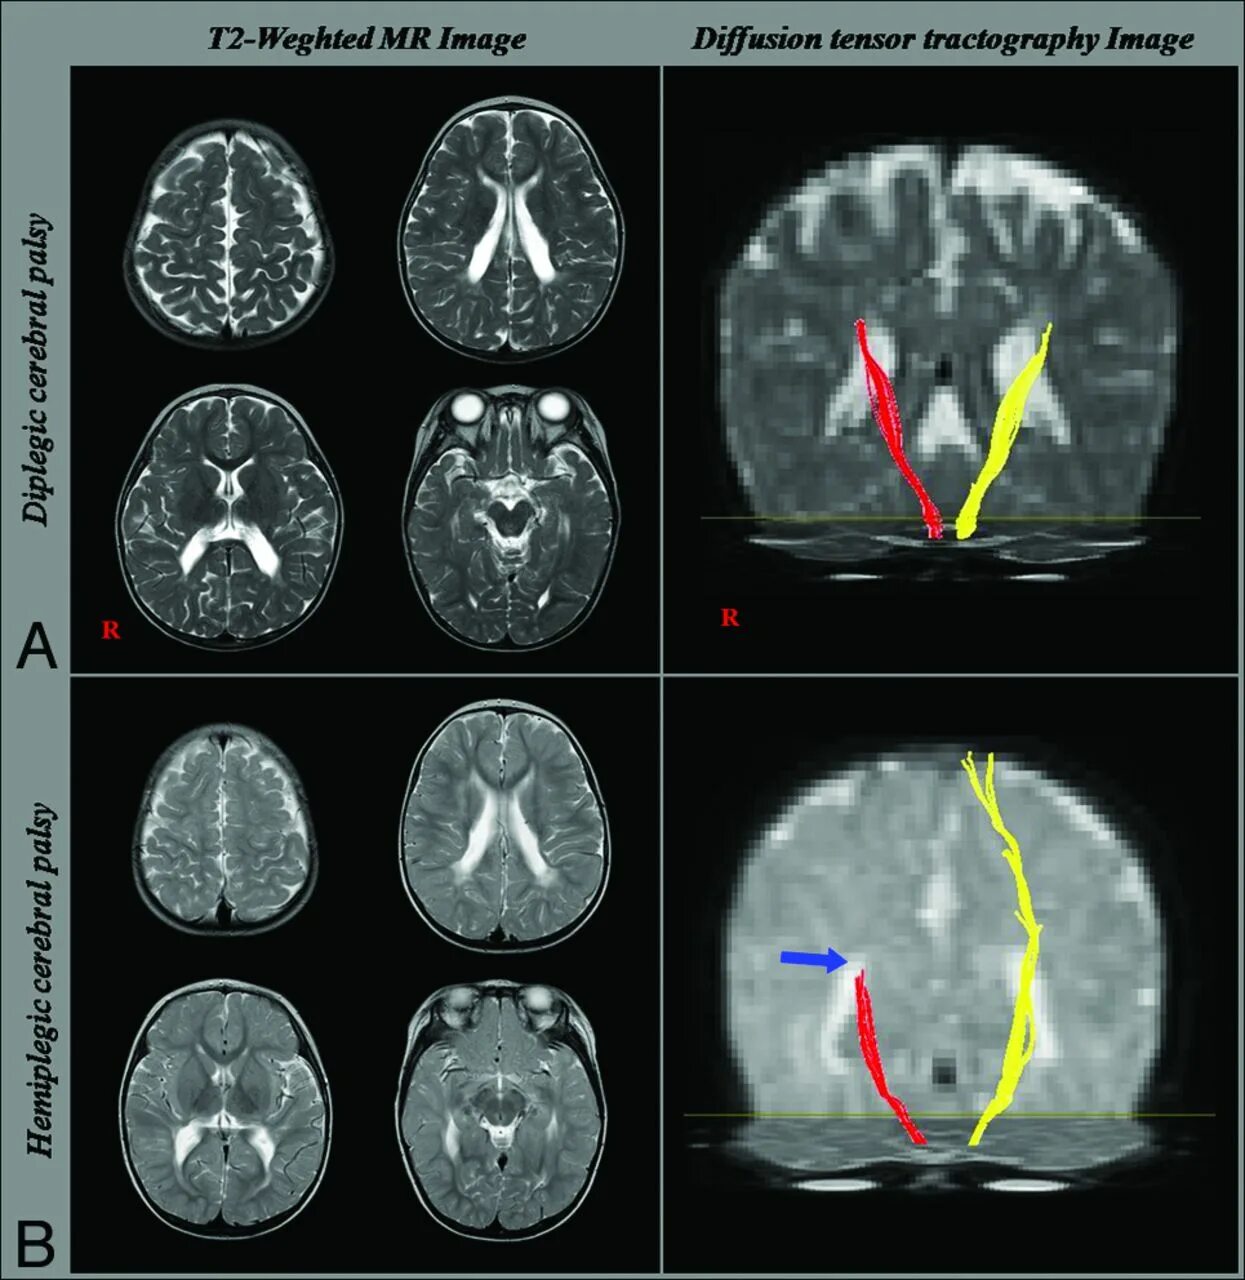

Diffusion tensor